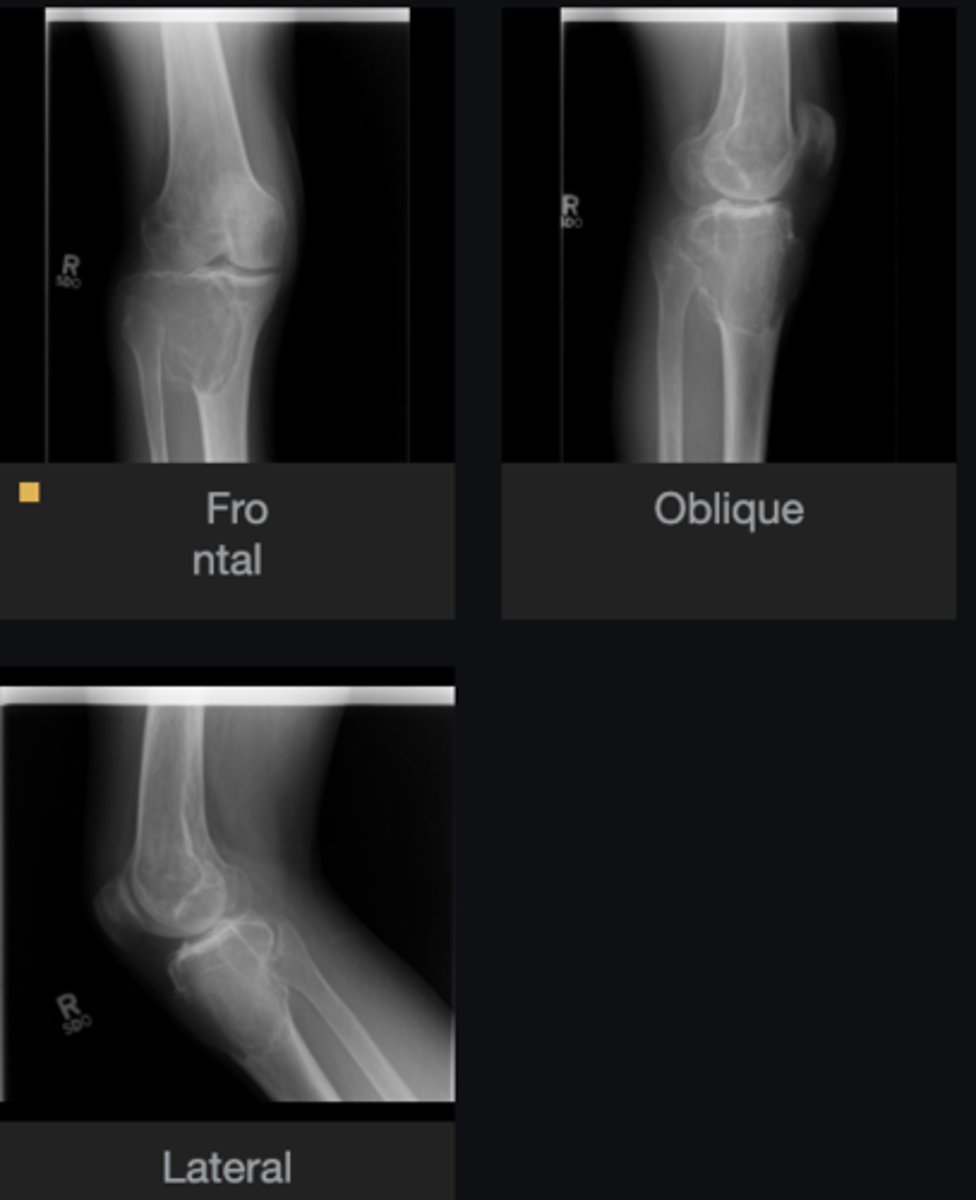

- Humerus

- Central

- Diaphysis

- Geographic

- Cortical thinning

Describe the lesion

<p>Describe the lesion</p>

Pathologic fracture

What complication has occurred?

<p>What complication has occurred?</p>

Simple bone cyst

Most likely diagnosis?

<p>Most likely diagnosis?</p>

Refer to orthopedist

Next step?

<p>Next step?</p>